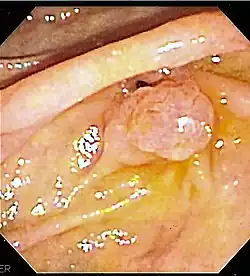

![]() The major duodenal papilla, seen on duodenoscopy at the time of ERCP. This is the protrusion of the ampulla of Vater into the duodenum. | |

The ampulla of Vater, hepatopancreatic ampulla or hepatopancreatic duct is the common duct that is usually formed by a union of the common bile duct and the pancreatic duct within the wall of the duodenum. This common duct usually features a dilation ("ampulla"). The common duct then opens medially into the descending part of the duodenum at the major duodenal papilla. The common duct usually measures 2–10mm in length.[1]

The ampulla of Vater is an important landmark halfway along the second part of the duodenum marking the transition from foregut to midgut.